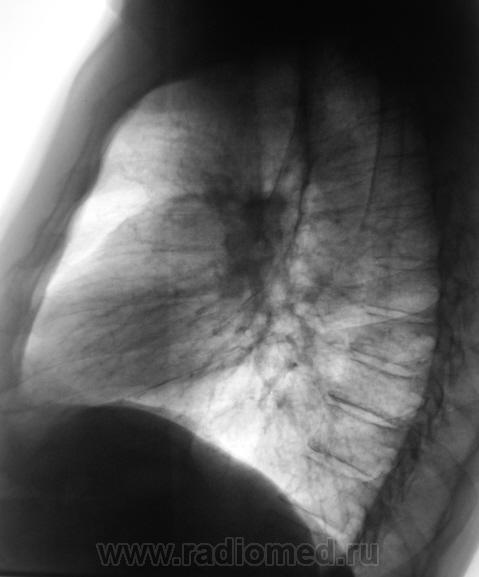

Пациент "взят на контроль" при расшифровке цифровых флюорограмм, дообследован - рентгенография в стандартных проекциях. Ваше мнение коллеги?

Произведены томограммы.

Пахнет периферическим c-r SIII лев. л-го, хотя на ТМГ он не получил должного отображения. Mts в лимфатич. узлы корня. Очаговые тени в легких вроде как связаны с сосудами...

MTS в правое и левое лёгкие, лимфатические узлы левого корня.